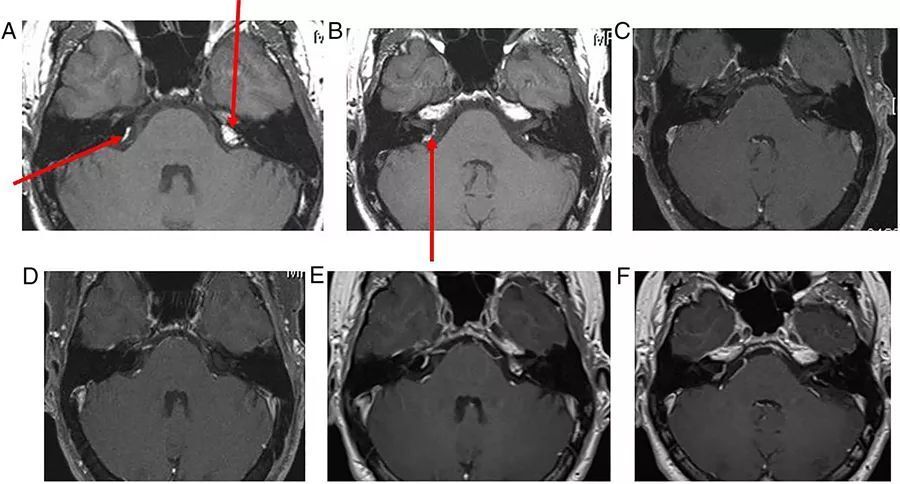

图10  右侧前庭神经鞘瘤。位于内听道基底部,向上延伸至耳蜗孔,病变随访3年以上未进展

图11  右侧面神经瘤。位于右侧内听道基底部,可见膝状神经节和内听道处强化肿物

图12  右侧舌咽神经/迷走神经鞘瘤。可见桥小脑角区域混杂信号的肿物,增强扫描可见显著强化,右侧小脑中脚受压变形,病灶向下延伸并进入颈静脉孔

图13  软骨肉瘤。可见肿物破坏颅底,以左内耳骨裂缝为中心,延伸至桥小脑角和海绵窦。其发源位置和T2W上的明亮信号表明它是一种软骨瘤,颅底的CT扫描骨窗证实了病灶的起源和骨质破坏的性质